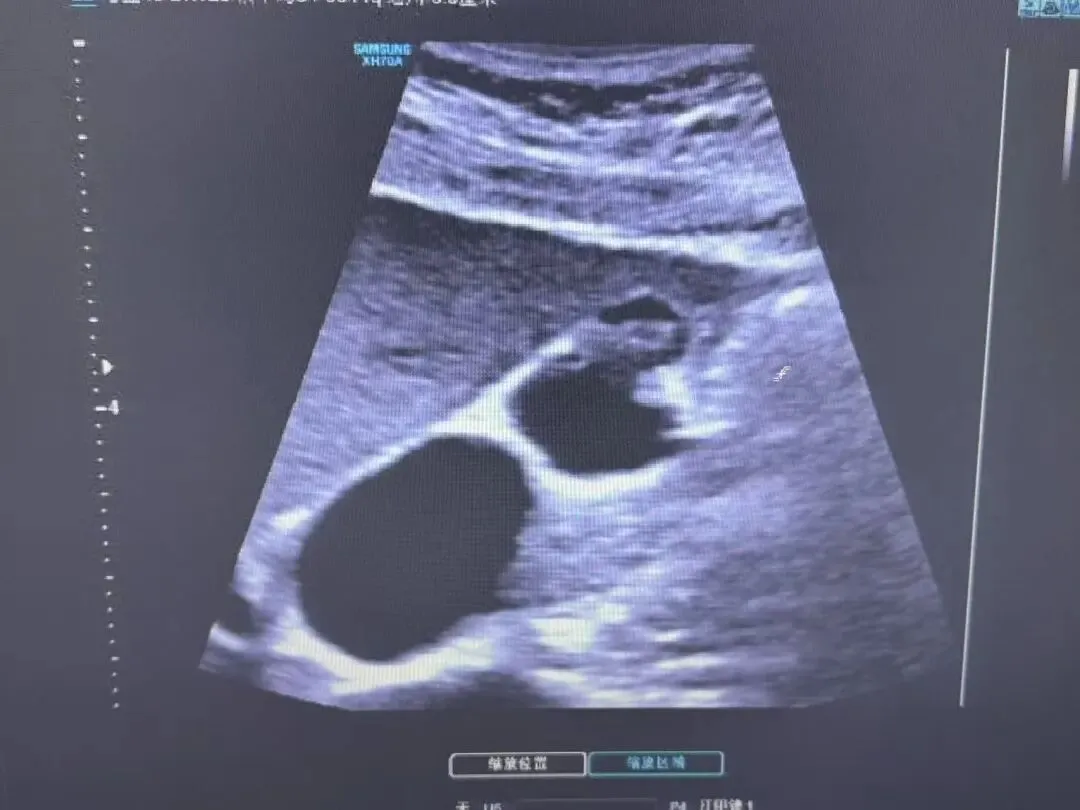

胆囊壁增厚,胆囊内透声差,其内稀疏或密集的细小或粗大光点

02

急性化脓性胆囊炎

胆囊肿大,胆囊壁增厚,胆囊内透声差,充满稀疏或密集的细小或粗大光点

囊壁增厚,呈“双边影”